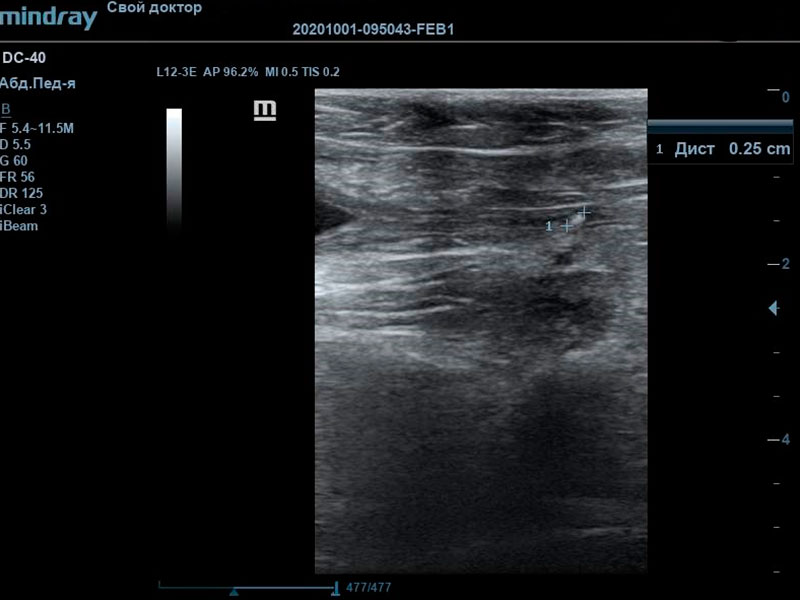

При проведении ультразвуковой диагностики врачом были выявлены крайняя степень наполнения мочевого пузыря, обильный пристеночный осадок с акустической тенью. Мочевой треугольник и проксимальная часть уретры также были расширены, в данной локации также визуализировались сформированные конкременты, размером до 3 мм. В почках определялись признаки билатеральной пиелоэктазии на фоне нарушения оттока мочи из мочевого пузыря.